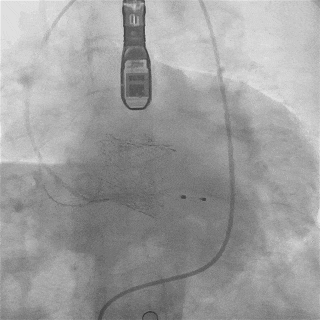

截止目前,临床试验进展顺利,入组已接近尾声。中期分析显示手术成功率和安全性指标均符合预期标准。

瓣膜功能、形态良好,未见反流